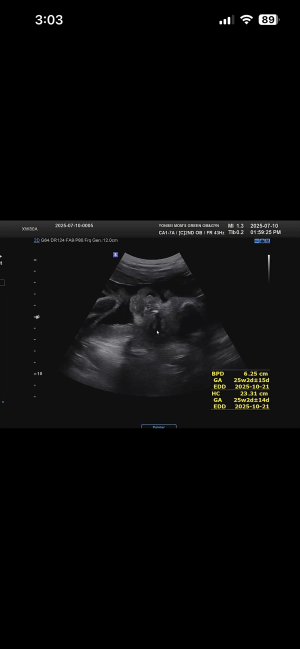

28주 입체초음파

닉네임_박*희_8

2025-09-18